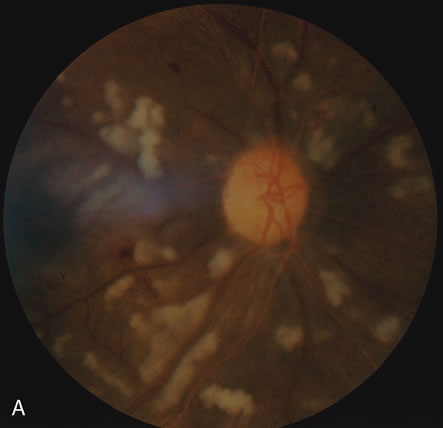

Even less common than retinopathy is lupus choroidopathy, of which only a few cases have been reported to date.214,224–226 Early autopsy studies demonstrated the frequent presence of mononuclear inflammatory cells in the choroid of patients with untreated SLE.208 The clinical changes seen in patients with lupus choroidopathy include serous elevation of the retina, most often of the neurosensory retina, serous elevations of the retinal pigment epithelium, and combined elevations of both (Fig. 7). These clinical findings are associated with systemic vascular disease, either hypertension because of lupus nephritis or systemic vasculitis.226 Treatment of the underlying disease, with systemic corticosteroids and immunosuppressive agents if needed, and control of any hypertension can resolve these serous retinal detachments.

Fig. 7. A. Fundus photograph and B. and C. fluorescein angiogram of a patient with choroidopathy and systemic lupus erythematosus. The fluorescein angiogram demonstrates multiple “smokestack” areas of fluorescein leakage. (Jabs DA, Hanneken A, Schachat AP, et al: Choroidopathy in systemic lupus erythematosus. Arch Ophthalmol 106:230, 1988. Copyright 1986, American Medical Association. Reprinted with permission.)